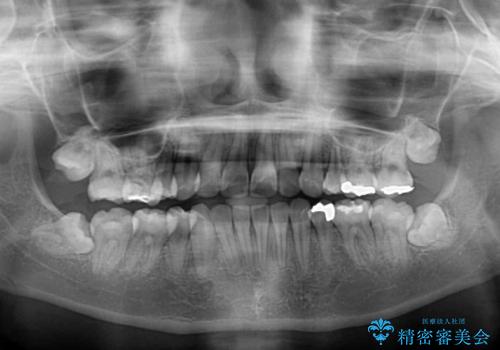

半年ほどで前歯のデコボコは改善され、汚れの溜まりやすさは解消されました。

抜歯スペースを閉じるために期間がかかりましたが、当初予定通り2年強で終えることができました。